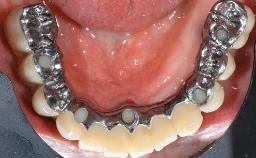

A 73-year-old woman was referred to the Division of Periodontology (University of Geneva School of Dental Medicine) after repeated unsuccessful treatment of a peri-implant infection. She was systemically healthy and did not smoke. The patient’s history revealed that, three years earlier, an immediate implant (Straumann Tapered Effect RN 4.8/4.1; Institut Straumann AG, Basel, Switzerland) had been inserted to replace the upper right central incisor. A metal-ceramic crown had been delivered using an adhesive resin cement. One year later, the patient had consulted another dentist due to discomfort in the soft tissues in the implant region. There was a suppurating peri-implant pocket, 10 mm deep. Peri-implant bone loss and excess luting cement were seen on the radiograph. The situation was treated with non-surgical debridement, amoxicillin, and repeated submucosal irrigation with a chlorhexidine digluconate solution. The patient was referred after the suppuration had persisted for several months.

Prosthodontic SAC classification

SAC Level Advanced

Defining Characteristics One missing tooth to be replaced by an implant-borne crown

Loading Protocol Conventional or early

Retention Cemented, with prosthesis margin > 3mm submucosal Cemented, with prosthesis margin > 3mm submucosal